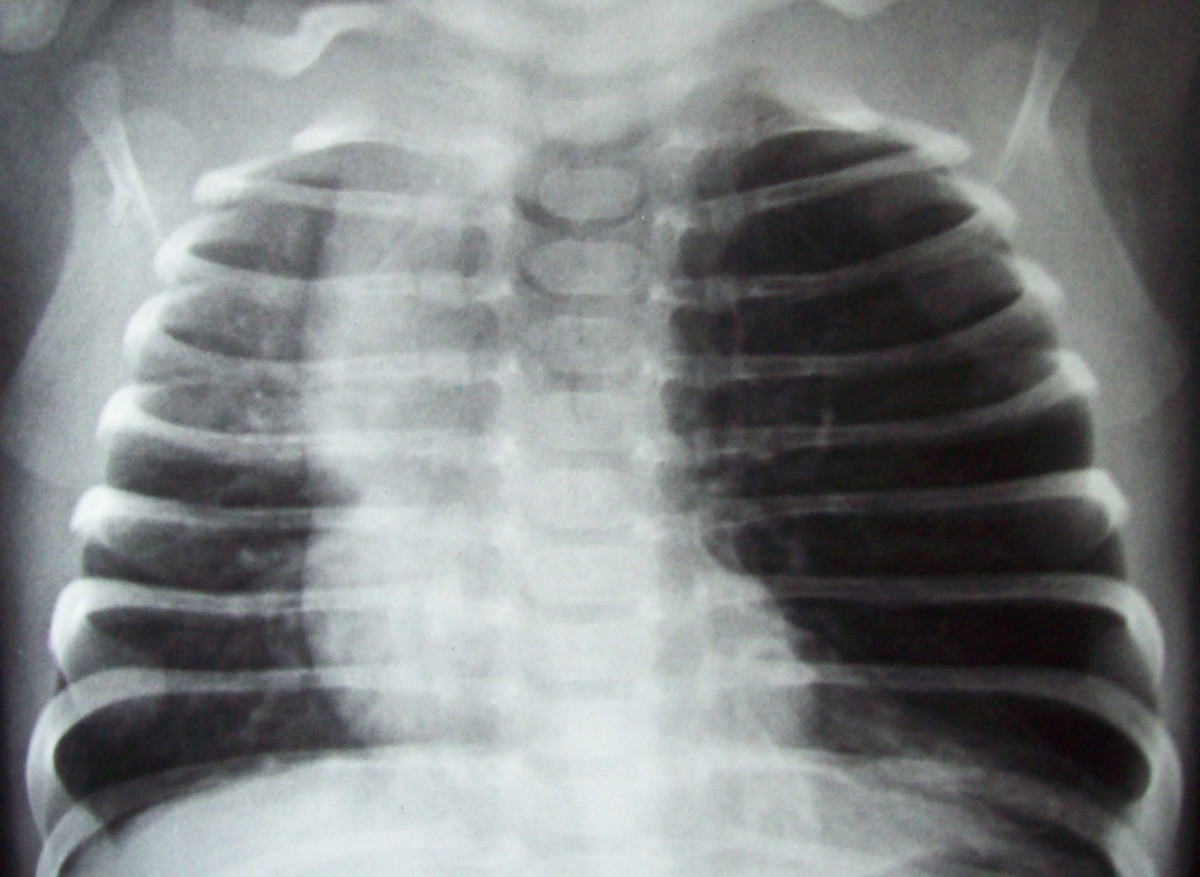

From roentgenrayreader.blogspot.com

Roentgen Ray Reader Congenital Lobar Emphysema Congenital Lobar Emphysema Chest X Ray Radiolucent expanded right lung in a newborn, compatible with congenital lobar emphysema (rml & rul). the hrct findings were characteristic of congenital lobar emphysema (cle). congenital lobar emphysema (cle). congenital lobar emphysema is a rare lung malformation, with an estimated incidence of one case per 20. congenital lobar emphysema (cle), also known as congenital alveolar overdistension,. Congenital Lobar Emphysema Chest X Ray.

LearningRadiology congenital lobar emphysema, cle Congenital Lobar Emphysema Chest X Ray Radiolucent expanded right lung in a newborn, compatible with congenital lobar emphysema (rml & rul). the hrct findings were characteristic of congenital lobar emphysema (cle). congenital lobar emphysema (cle). congenital lobar emphysema is a rare lung malformation, with an estimated incidence of one case per 20. congenital lobar emphysema (cle), also known as congenital alveolar overdistension,. Congenital Lobar Emphysema Chest X Ray.